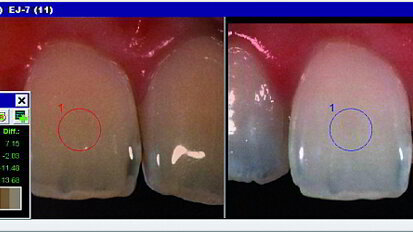

Identifier si, oui ou non, votre patient est vraiment hypersensible des dents par rapport à une crise d'anxiété dentaire pouvait ...